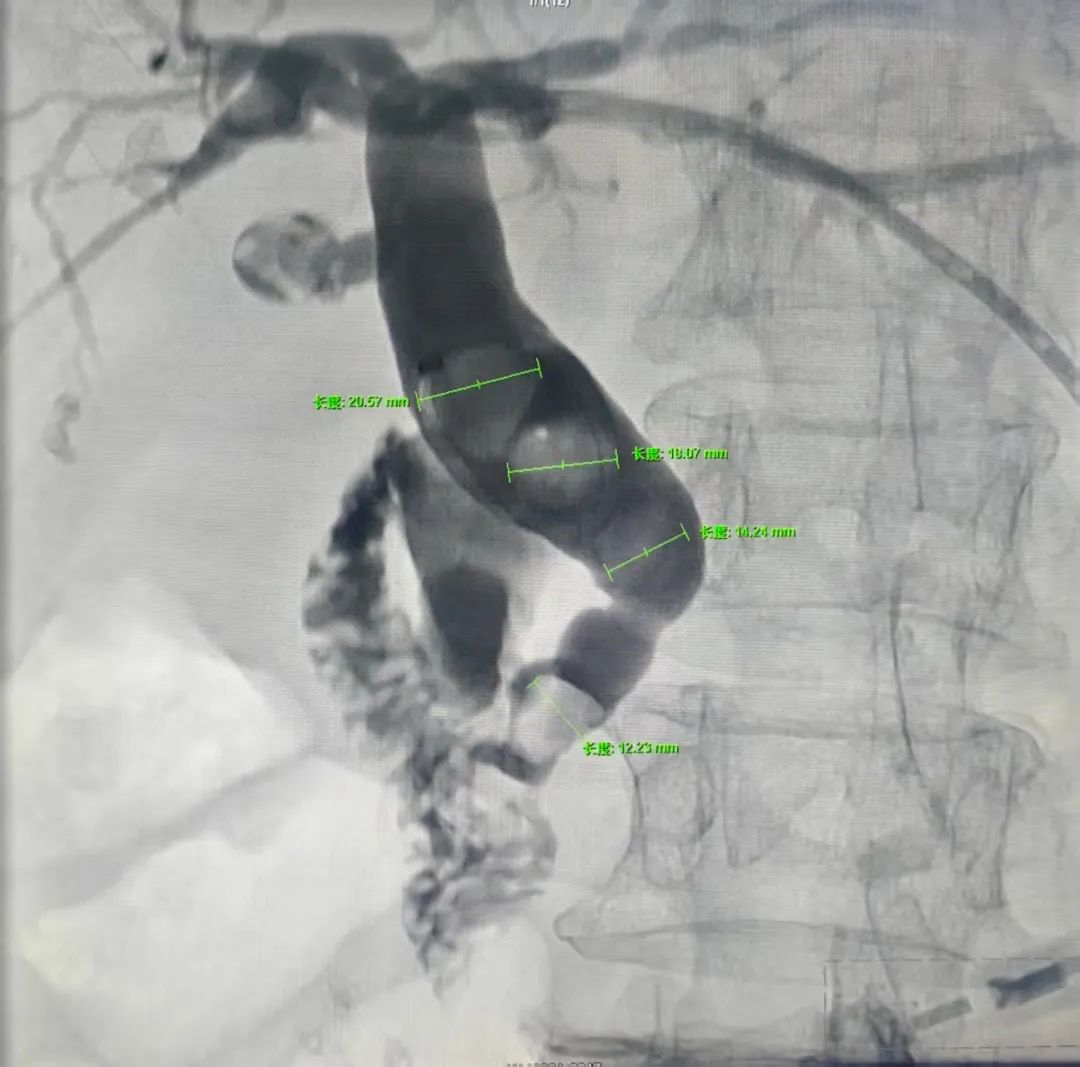

对李奶奶,诸城市中医医院决定采用微创介入胆管脓液引流术。术中,在超声引导下确定了穿刺点,局麻后利用几乎无创的办法,十分钟完成了胆管的穿刺置管引流,脓液从2毫米的小孔和细管中迅速排出,随之体温下降,感染性休克解除。又经过引流、抗炎慢慢恢复身体机能后,诸城市中医医院采用球囊扩张壶腹部胆管出口,然后把胆管内最大直径近20毫米的4块结石全部推送到肠道内随粪便排出体外,彻底解决了结石阻塞引起胆管发炎的病根,彻底治愈结石病,老人完全恢复了健康。

对年近百岁的赵奶奶诸城市中医医院采用了微创介入支架植入术。术中,完成肝内胆管的穿刺造影后找到胆管癌梗阻部位,置入胆道支架开通胆管,解除了梗阻,然后把穿刺的通道堵上,手术完成,不但患者黄疸得到了解除,而且患者外表不留任何引流管,做到完全无创。术后赵奶奶回去自在生活了半年多以后,十二指肠出现完全梗阻,吃不下饭了,再次回来后诸城市中医医院又经口引入一枚肠道支架,和做个胃镜一样简单开通了肠道,解决了吃饭问题。目前老人恢复如初,能吃能喝,平安地过了这个春节,如今已经是百岁老人了。

微创介入支架植入术